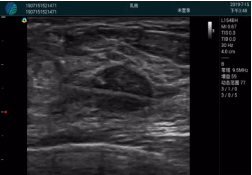

腺體內(nèi)部清晰顯示一低回聲塊影,形態(tài)不規(guī)則,邊界模糊,邊緣呈毛刺狀,內(nèi)部見砂礫樣鈣化

M20引導(dǎo)下穿刺活檢術(shù)

M20引導(dǎo)下平面內(nèi)穿刺取出的腫塊組織

甲狀腺囊性結(jié)節(jié),囊壁鈣化,透聲好

甲狀腺囊性占位